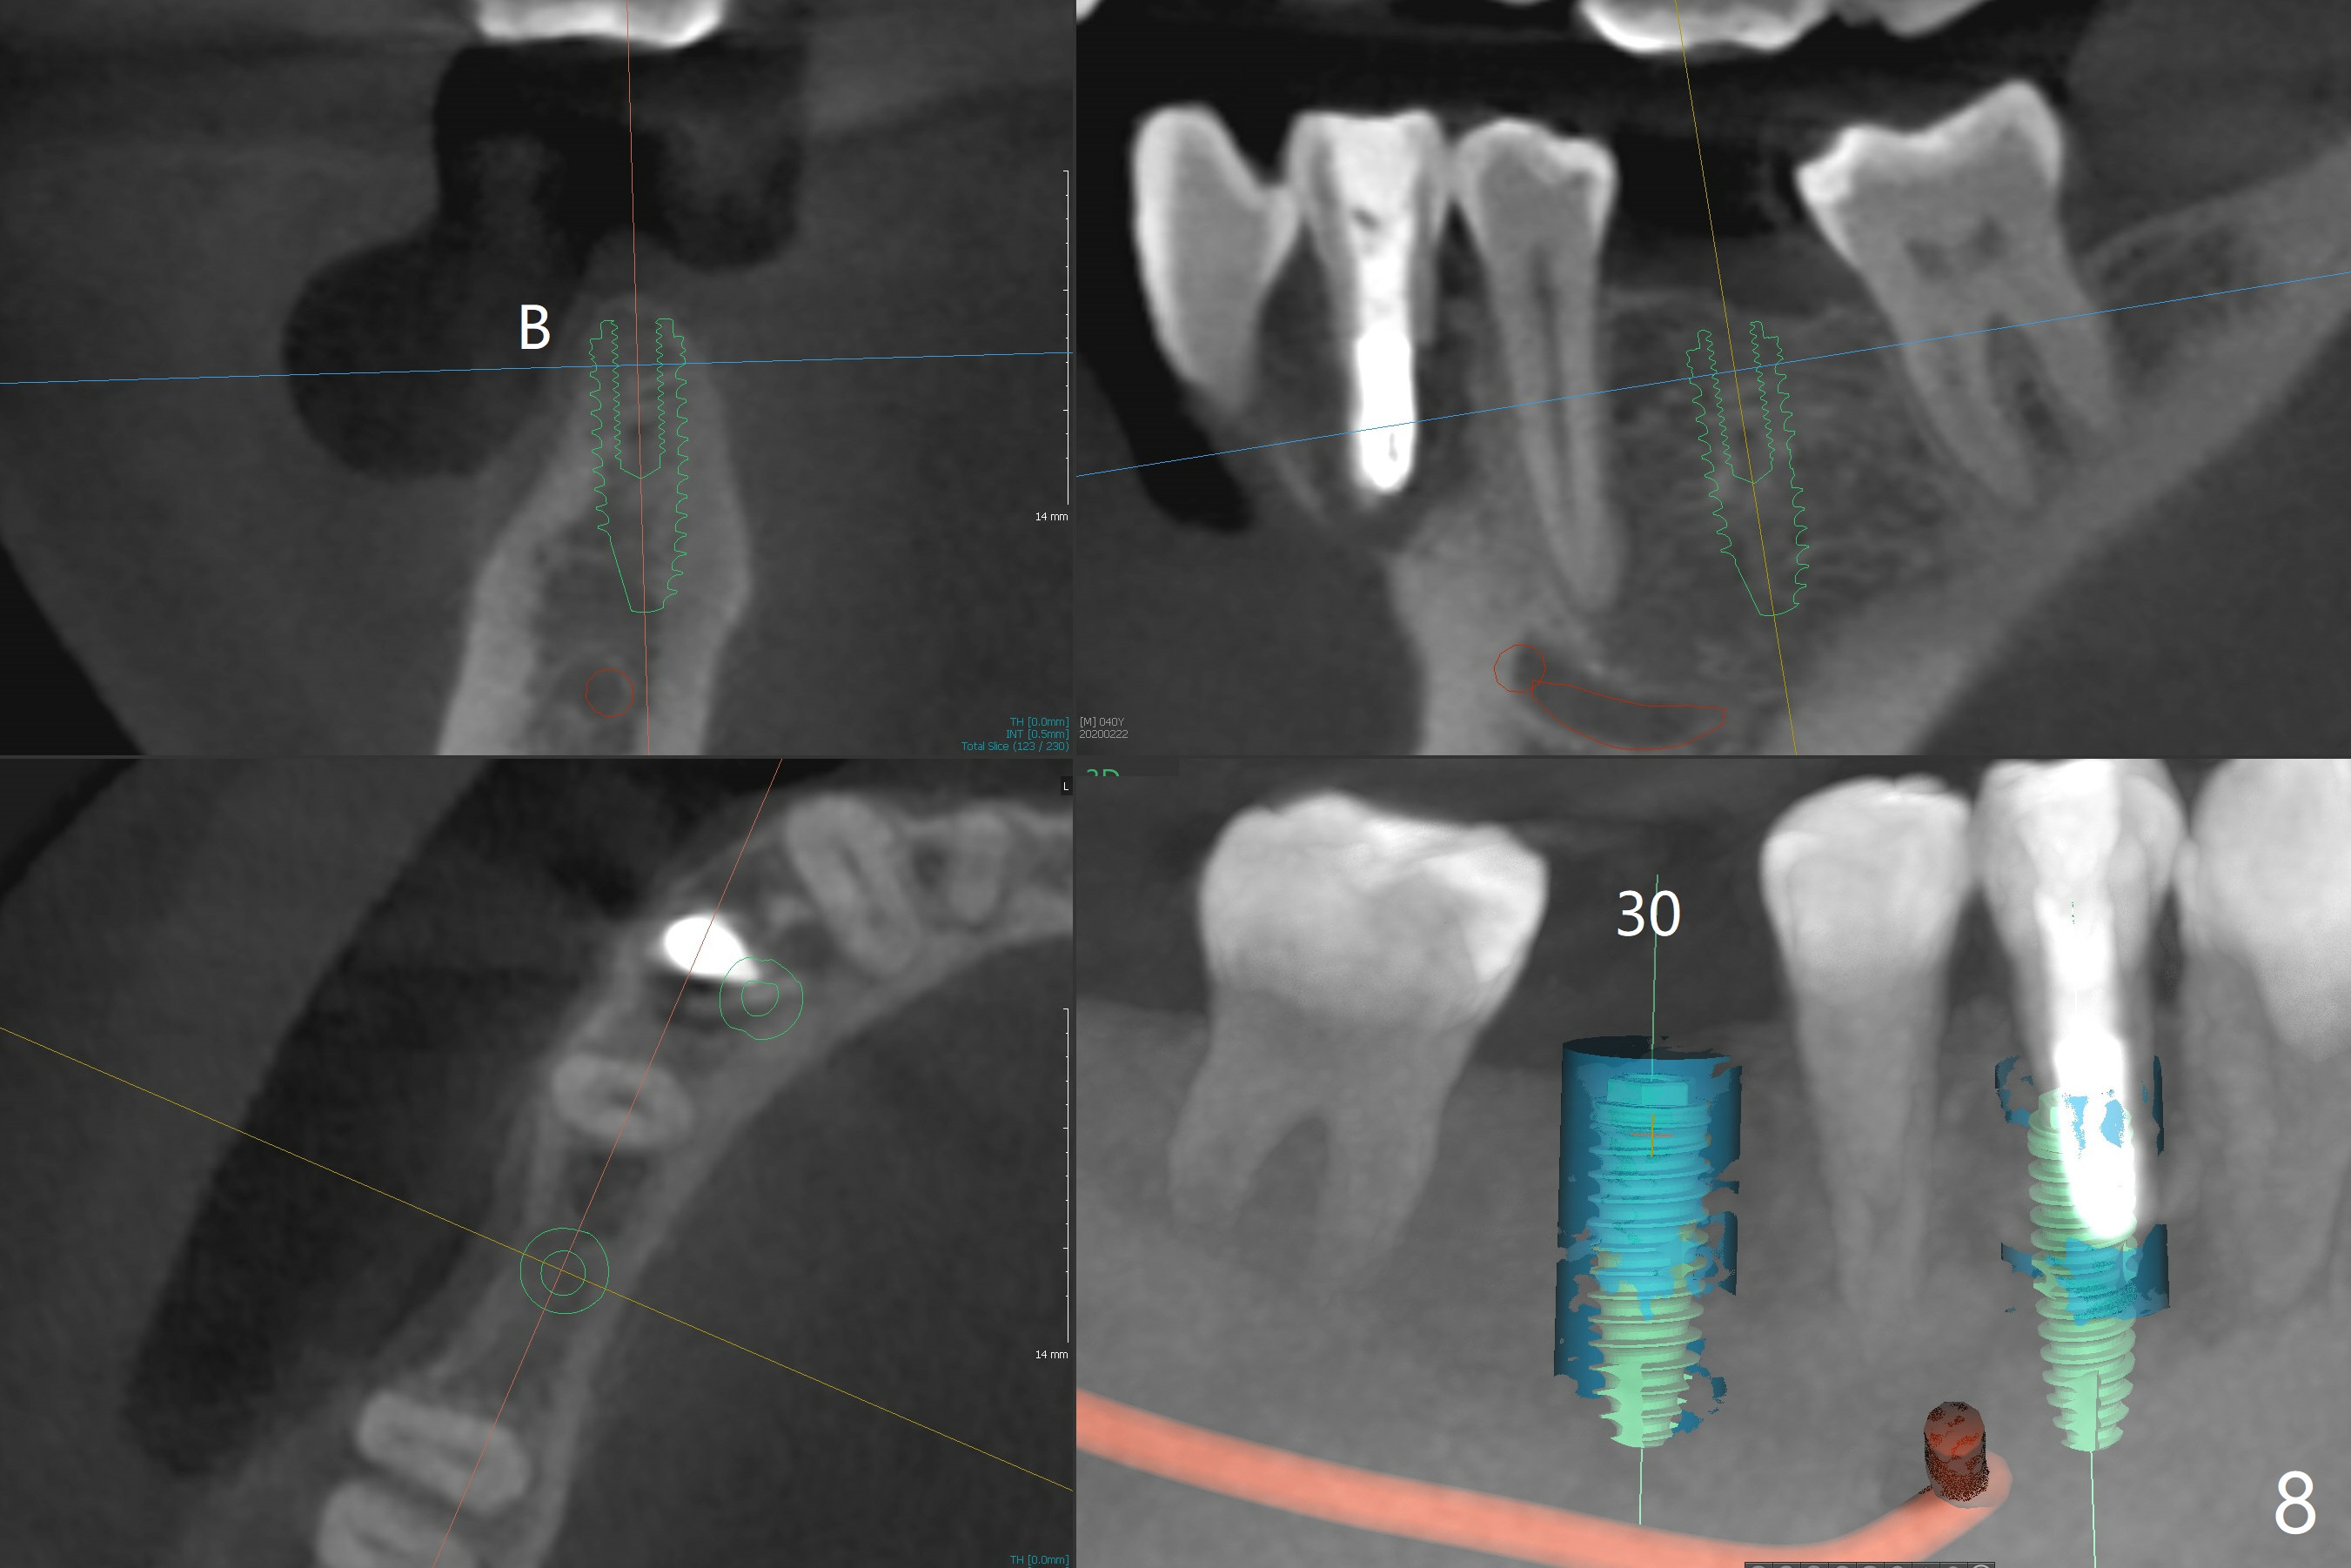

The ridge at #30 is narrow (~ 4 mm buccolingual and ~7 mm mesiodistal, Fig.8). A 4x11.5 mm will be placed. Impression will be taken for guides for #28 and 30. Incision will be made prior to guide seating (Fig.9 occlusal view); initial osteotomy (Fig.10 black circle) will be conducted with guide clockwise (white curved arrow). With removal of the guide, the ridge is split (Fig.11 black line). Osseocondensation drills will be used for ridge expansion with the help of guide (in the middle of the metal sleeve, Fig.12 counterclockwise).